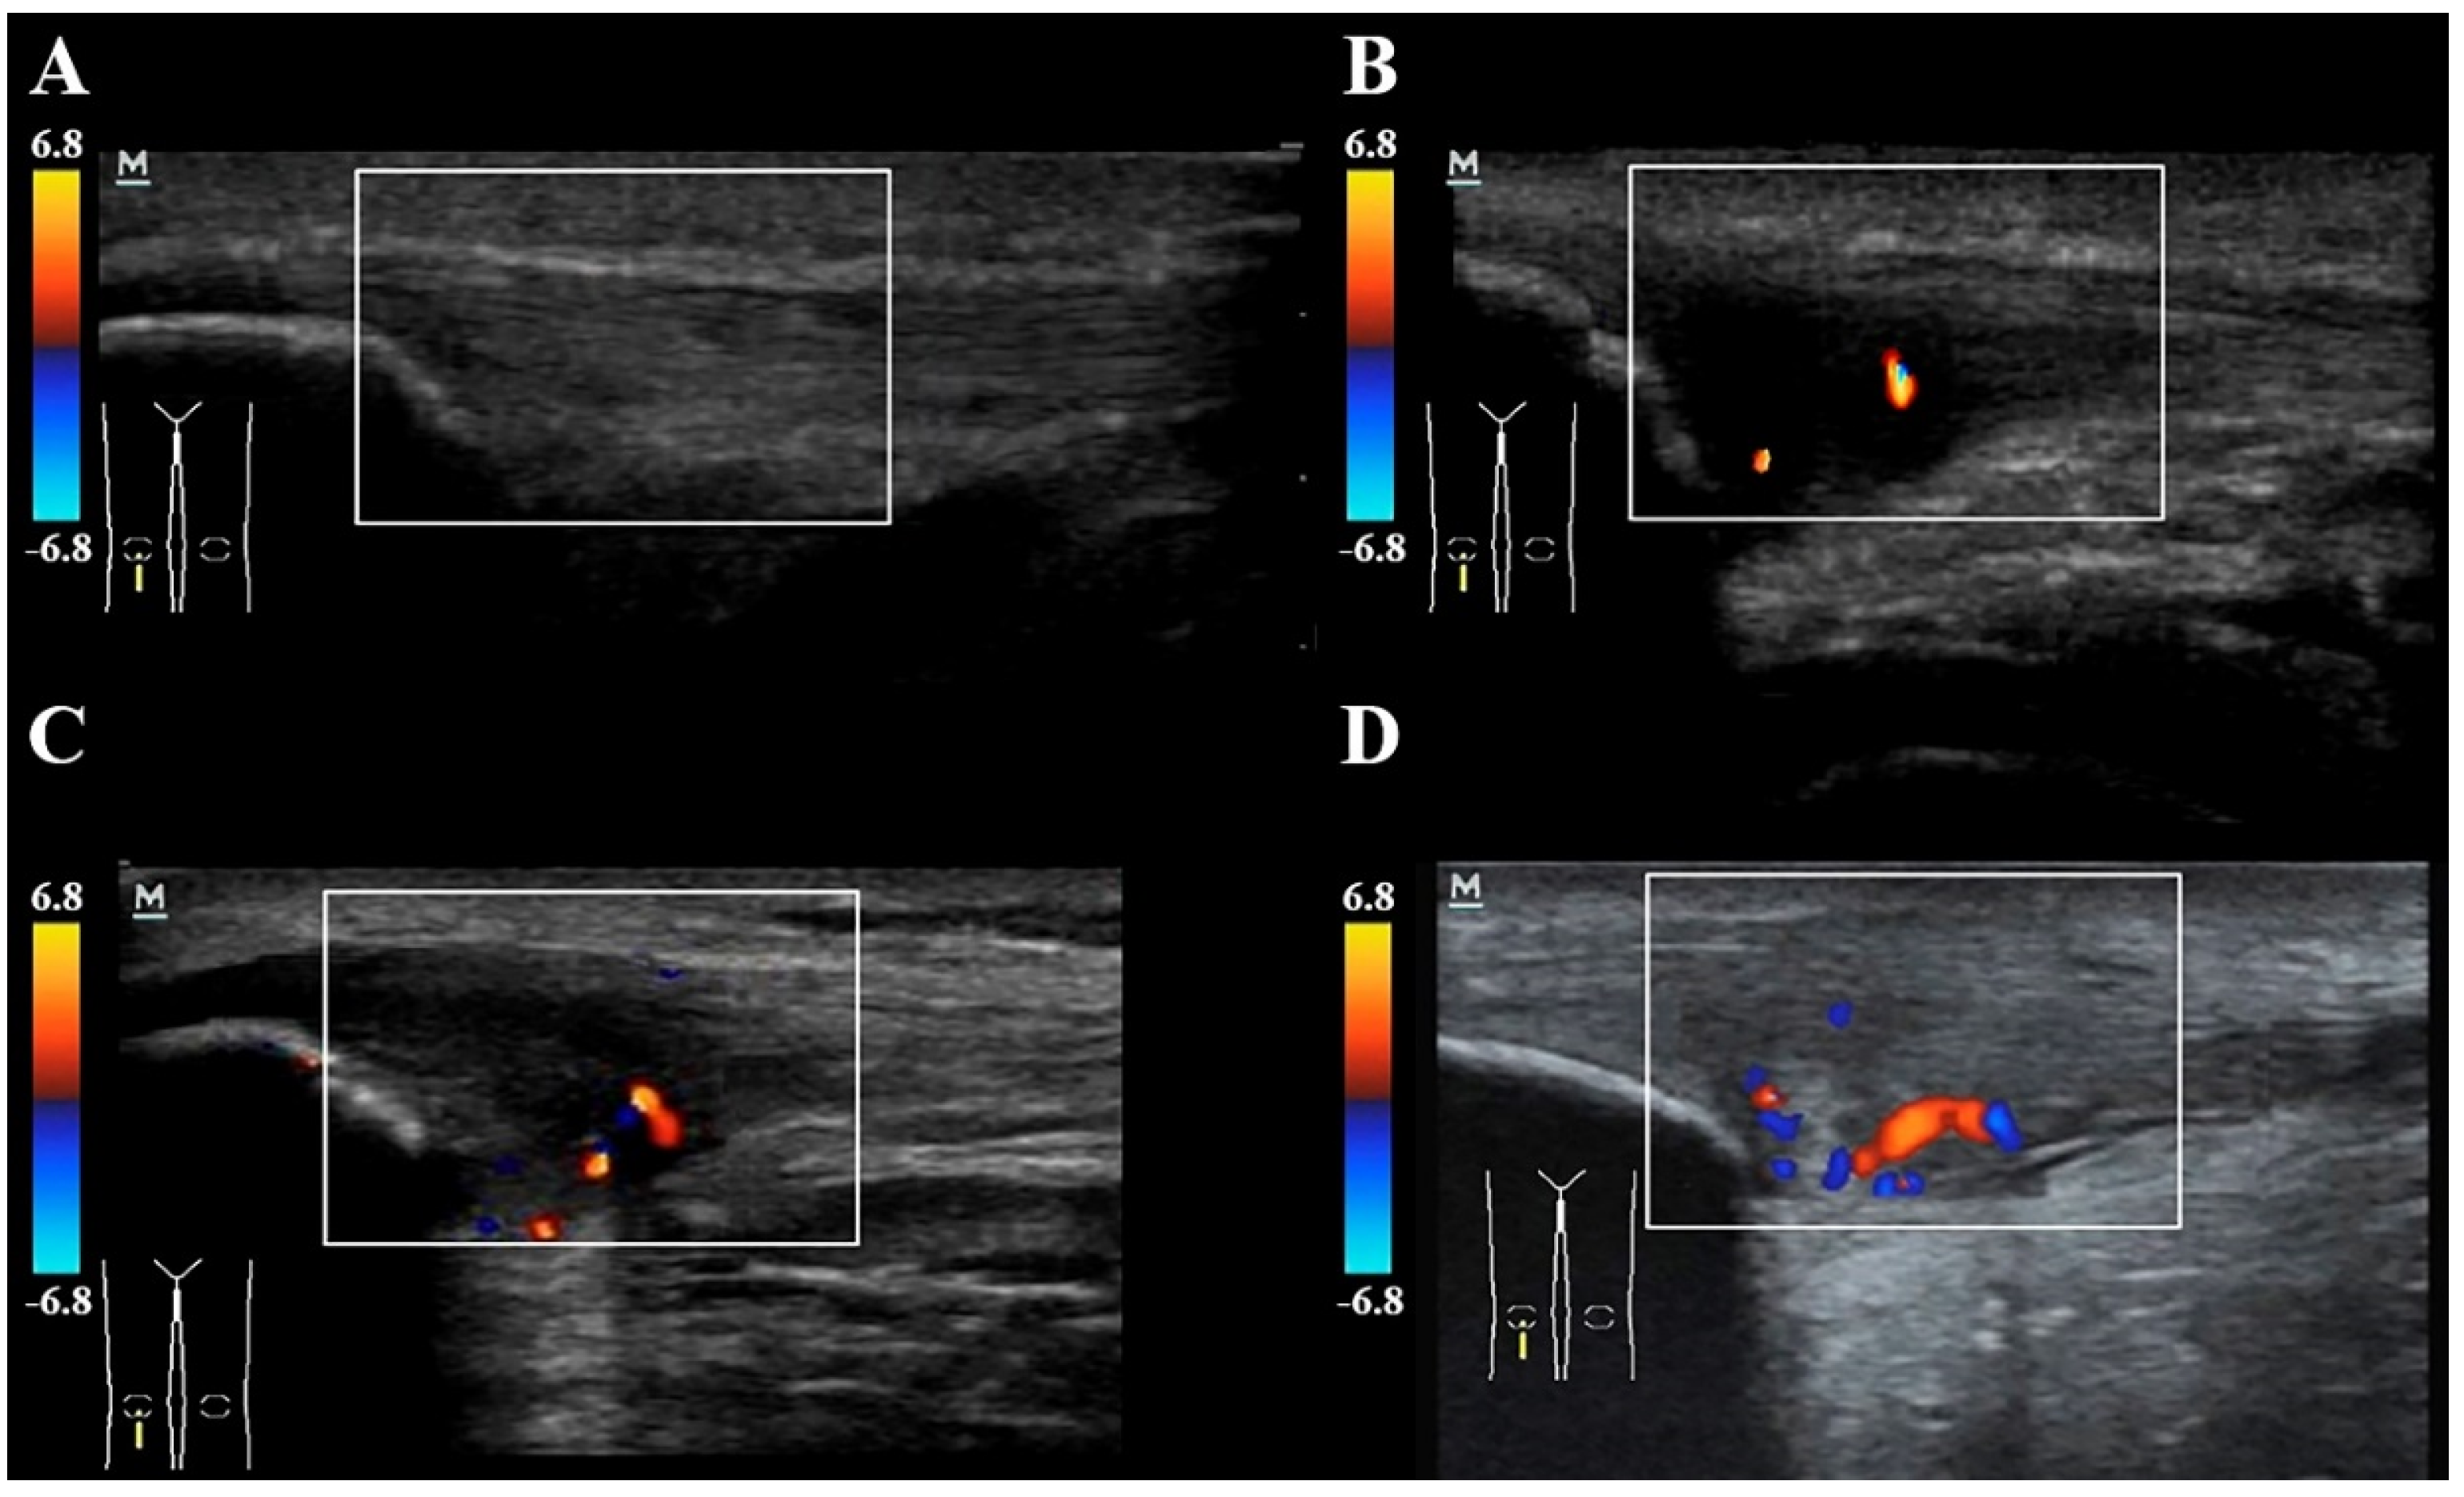

2.4. Neovascularization and Doppler Assessment of the Patellar Tendon

- Gisslen, K.; Alfredson, H.; Peers, K. Neovascularisation and pain in jumper’s knee: A prospective clinical and sonographic study in elite junior volleyball players * Commentary. Br. J. Sports Med. 2005, 39, 423–428. [Google Scholar] [CrossRef]

| Vascularization grading system Grade 0 Grade I Grade II Grade III Grade IV | 20; 100% - - - - | 6; 30% 10; 50% 4; 20% - - | |